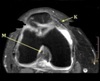

1

What is letter A?

SUPRASPINATUS TENDON

Q

A

3

CORACOID PROCESS

4

What is letter B?

DELTOID MUSCLE

5

What is letter C?

INFRASPINATUS MUSCLE

6

What is letter D?

SUPRASPINATUS MUSCLE

7

SUBSCAPULARIS MUSCLE

8

HEAD OF HUMERUS

9

10

GLENOID

11

ANTERIOR LABRUM